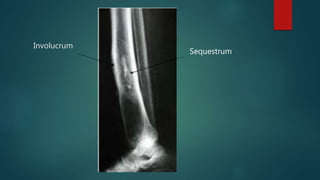

CHRONIC OSTEOMYELITIS

๏ต Sequestrum, Involucrum, abscess or sinus (cloaca) is present

๏ต Sequestrum is the necrotic

bone embedded in the

pus/infected granulation

tissue

๏ต Involucrum is the new bone

laid down by the

periosteum that surrounds

the sequestra.

Involucrum

Sequestrum